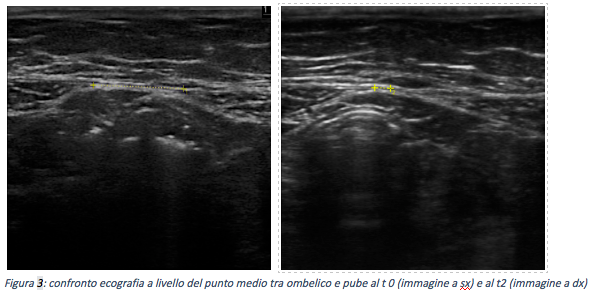

È stato impostato un programma riabilitativo volto principalmente al rinforzo dei muscoli del pavimento pelvico e del trasverso dell’addome. Il fisioterapista ha effettuato una valutazione ecografica dell’eco-struttura del muscolo trasverso dell’addome e delle due parti che compongono il muscolo retto dell’addome.

Inoltre è stata fatta una valutazione funzionale, sempre con l’uso dell’ecografo, dell’attivazione di questi due muscoli durante alcuni esercizi a lettino.

Successivamente è stato impostato un programma di allenamento e mantenimento (sedute da 60 minuti con frequenza bisettimanale). Per verificare i progressi, ad ogni seduta fisioterapica sono state effettuate le misurazioni della diastasi in tre punti diversi dell’addome:

Risultati A circa due mesi dalla presa in carico della paziente si è osservata una riduzione importante della diastasi addominale confermata dalle misurazioni rilevate e dalla documentazione fotografica in basso (tempo 0: presa in carico della paziente; tempo 1: a un mese dall’inizio del trattamento; tempo 2: a due mesi dall’inizio del trattamento). Inoltre si è constatata la risoluzione completa dell’incontinenza urinaria.